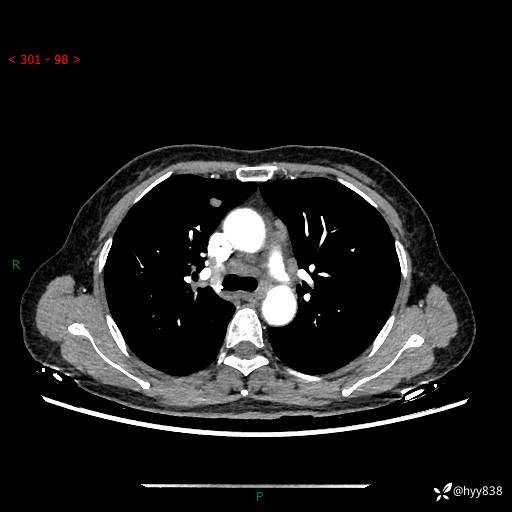

【患者信息】:58岁/女

【主诉】:体检发现肺结节

【检查】:胸部CT平扫+增强